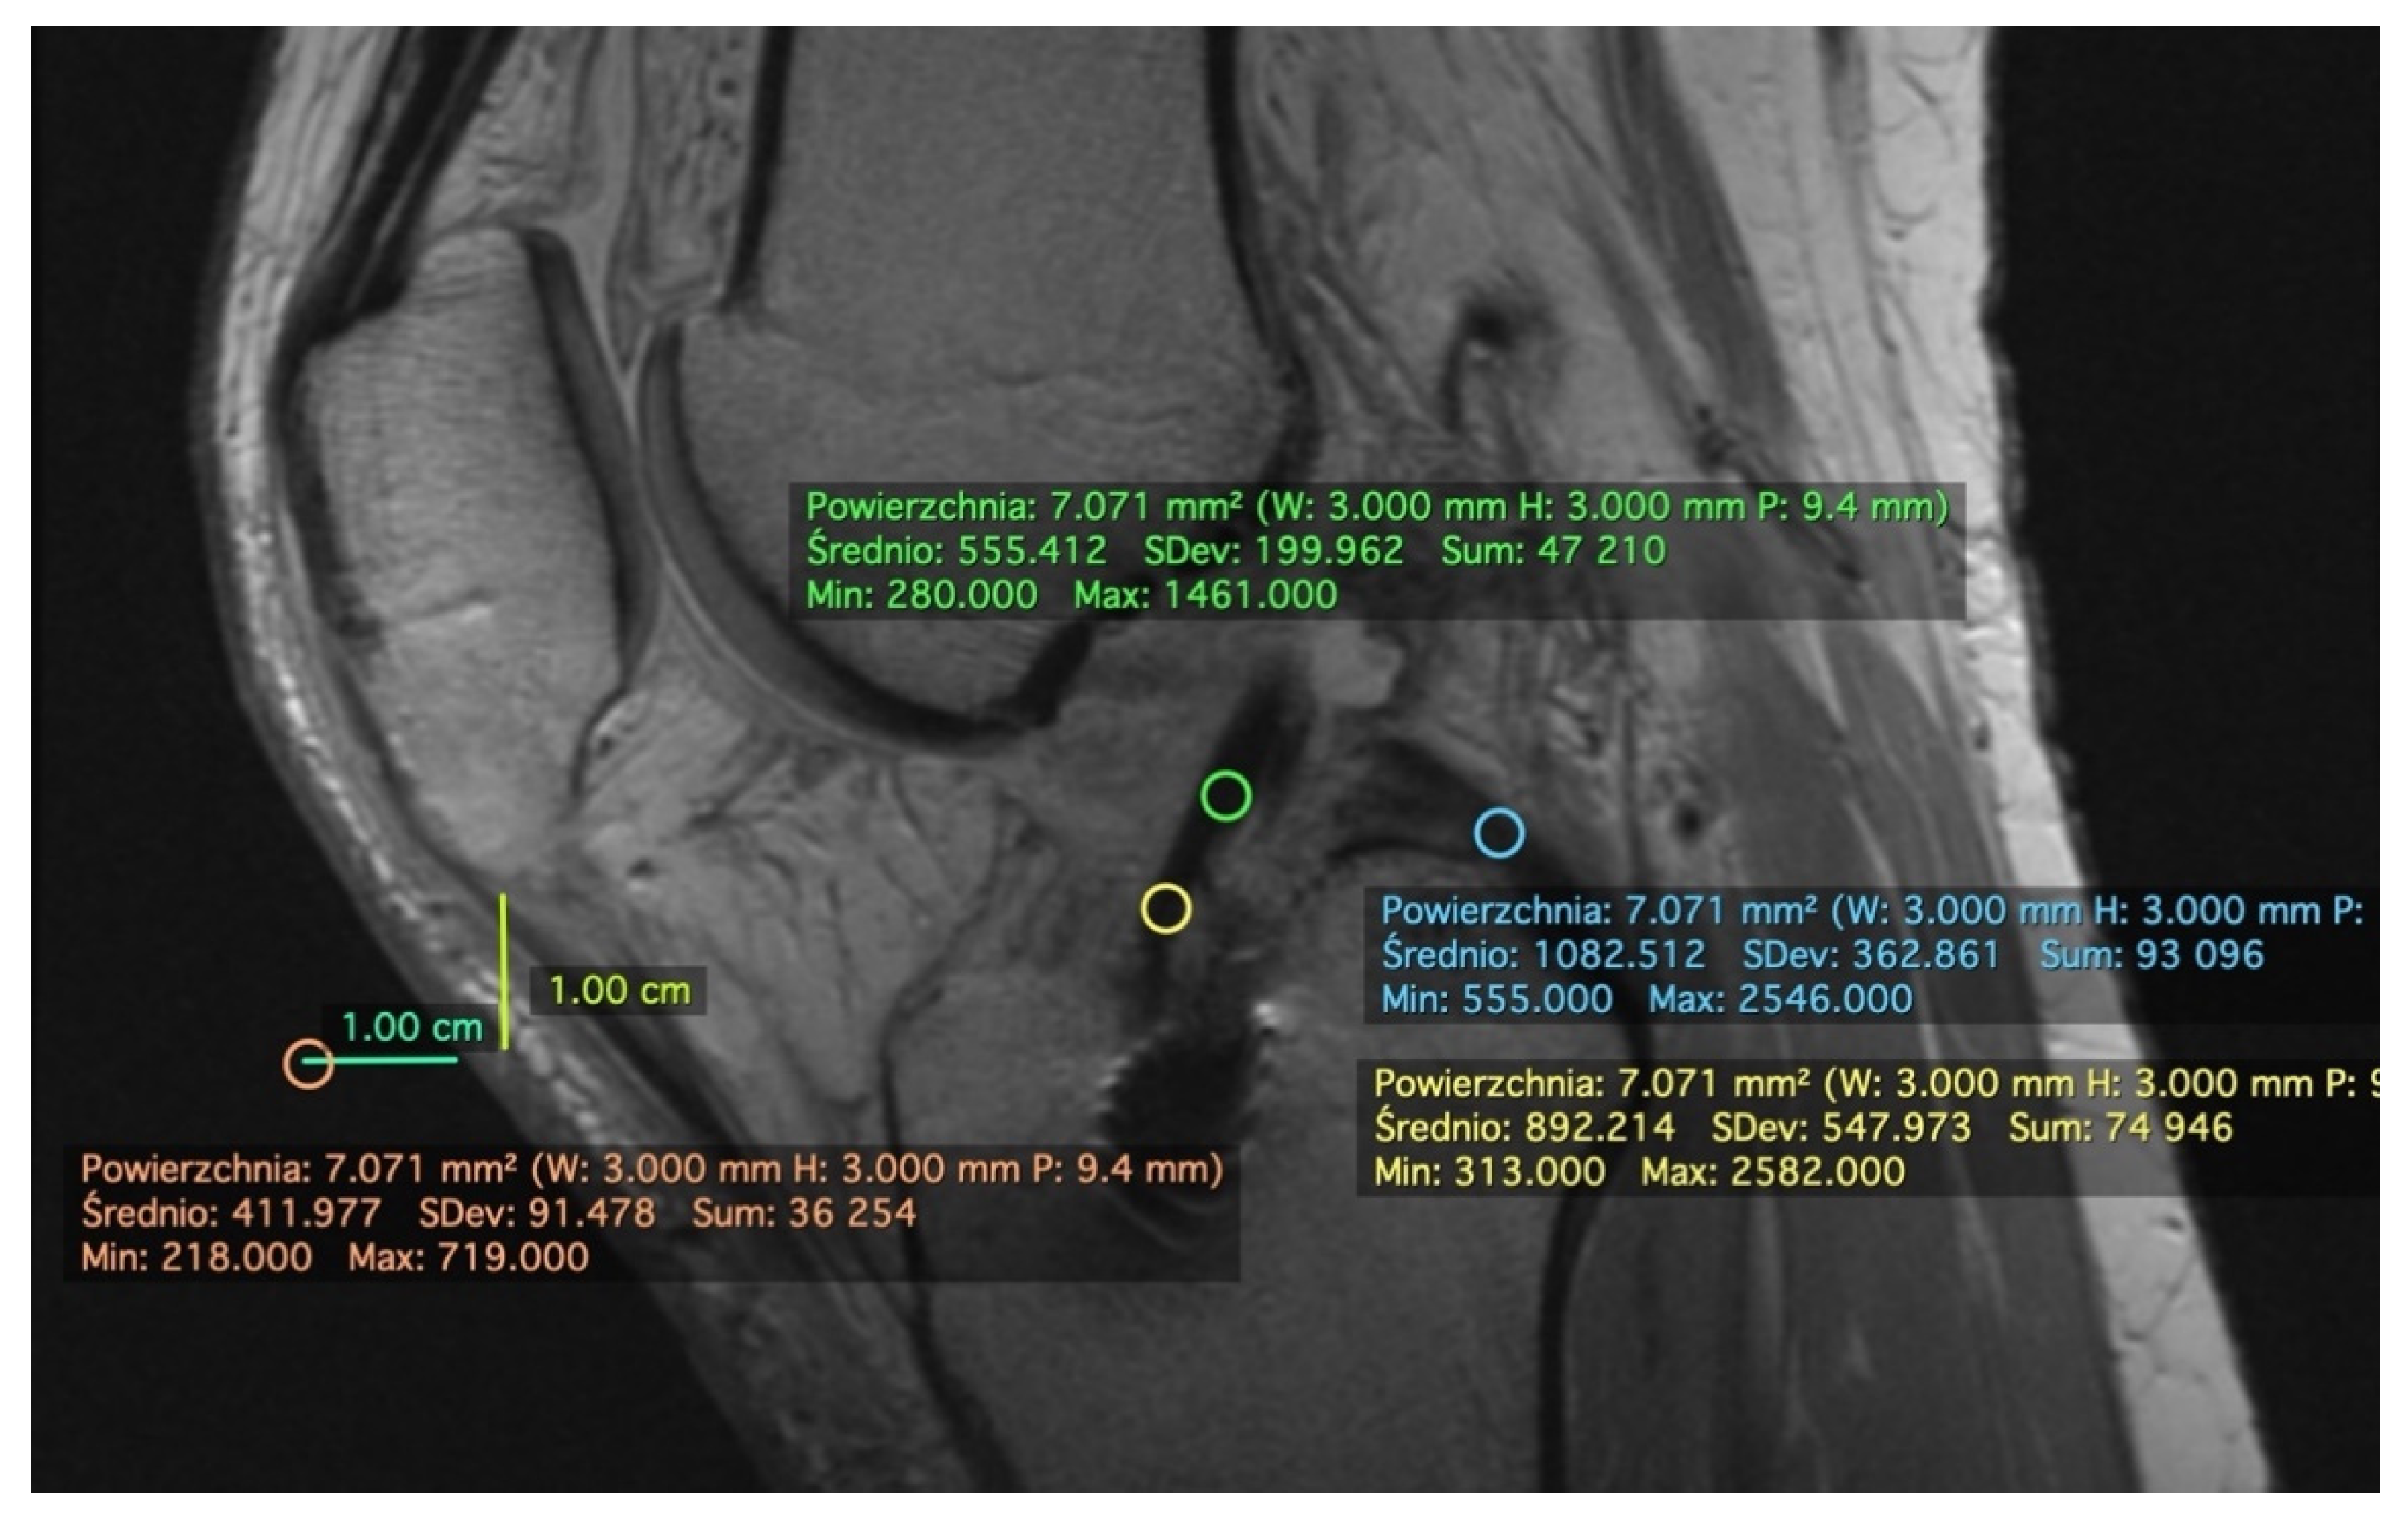

2.1. Measurement on the Sagittal Plane

2.3. Standard Deviation (SD)